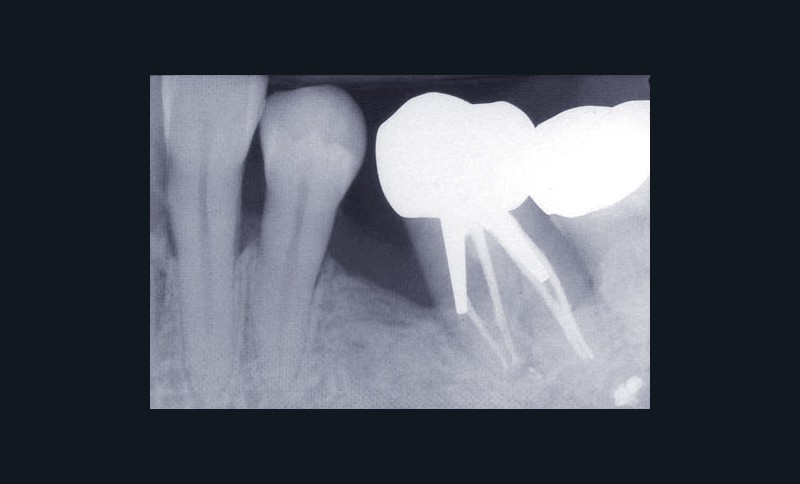

Une patiente âgée de 45 ans consulte à la fin des années 1990 avec une contention en échelle au maxillaire afin de soulager les mobilités des dents antérieures.

Les examens cliniques et radiographiques montrent une parodontite chronique généralisée (fig. 1a à m).

Nous décidons d’entreprendre une thérapeutique initiale parodontale classique dans tous les secteurs, y compris l’extraction de 24, un bridge de 45 à 48 avec 46 en pontique, un bridge complet de contention de 17 à 27 sur 11 piliers dentaires et une greffe épithélio-conjonctive sur 31. Cette dernière ne sera jamais réalisée. Le bridge maxillaire permettra de réduire le surplomb antérieur et d’améliorer le sourire de la patiente, ce qui constitue l’une de ses demandes.